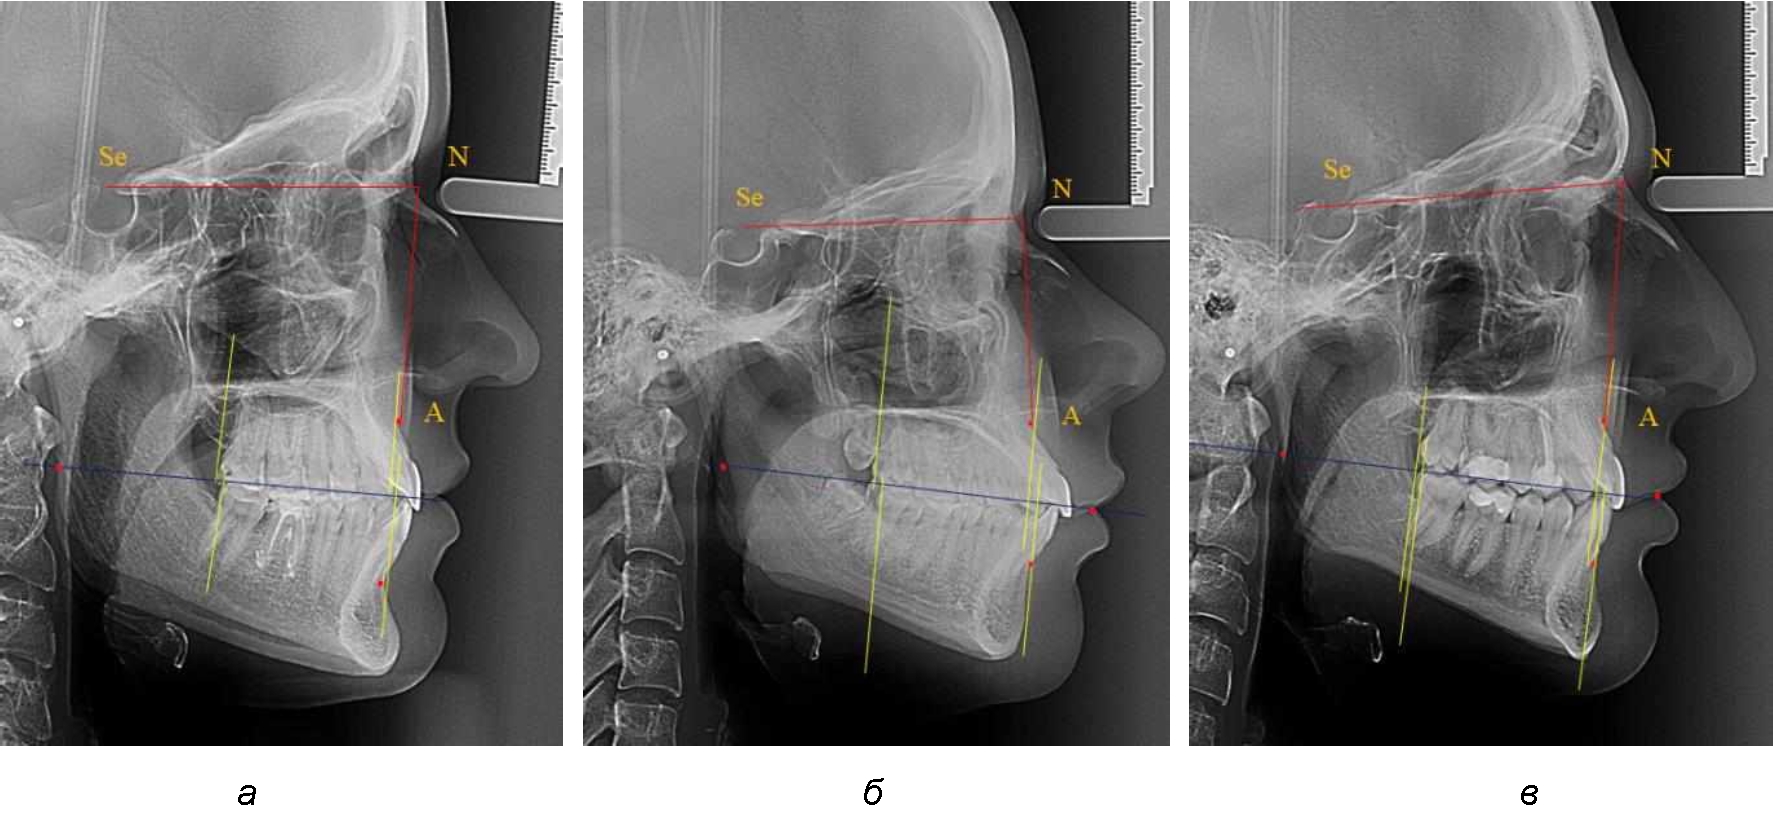

При сагиттальной патологии прикуса встречались варианты, при которых отмечалось равенство либо не равенство альвеолярно-ден-тальных размеров челюстей. Однако вне зависимости от этого, как правило, была отмечена разница в положении челюстей, измеряемая от конструируемой точки «rmРOcP» до точек апикальных базисов по Downs. С дистальной окклюзией было 20 снимков и с мезиальной окклюзией – 19 снимков.

Характерной особенностью мезиальной окклюзии было увеличение расстояния между проекционными апикальными точками, при котором существенно смещалась кпереди нижняя челюсть, а Wits-число имело отрицательные значения. Также дистальная точка нижнего моляра была расположена кпереди от верхней дистальной точки окклюзии второго моляра. Относительно равными считались показатели альвеолярно-дентальных размеров, при которых разница не превышала 1,5 мм. Тем не менее расстояние «rmРOcP-B(SM)» превышало расстояние «rmРOcP-A(SS)» в среднем по группе на (6,87 ± 1,62) мм, что свидетельствовало об аномалии положения челюстей, при котором визуально нижняя челюсть располагалась впереди верхней челюсти (рис. 3).

Рис. 3. Положение апикальных точек и челюстей при мезиальной окклюзии с равными (а) и разными (б) альвеолярно-дентальными размерами зубо-челюстных дуг

В тех случаях, когда при мезиальной окклюзии альвеолярно-дентальные размеры были различными, размер нижней челюсти превышал аналогичный параметр верхней челюсти в среднем на (3,74 ± 1,28) мм.